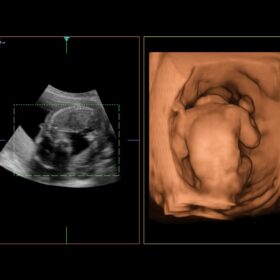

Cardio 2D, Color, PW, CW and TDI mode

Obstetrics 2D, Color and 4D mode

- In OB/GYN, high-resolution B-mode imaging coupled with eFLOW. The advanced flow mapping mode that offers increased sensitivity to flow in minute vessels, facilitates accurate assessment of fetal well-being. In addition, ARIETTA is equipped with a diverse range of advanced functions including Dual Gate Doppler. Valuable for diagnosing fetal arrhythmia, and STIC, providing morphological observation of the fetal heart.